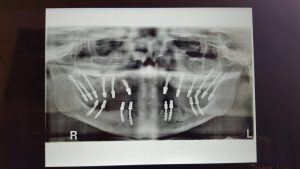

implant-dentar-bacau-iovan februarie (25)